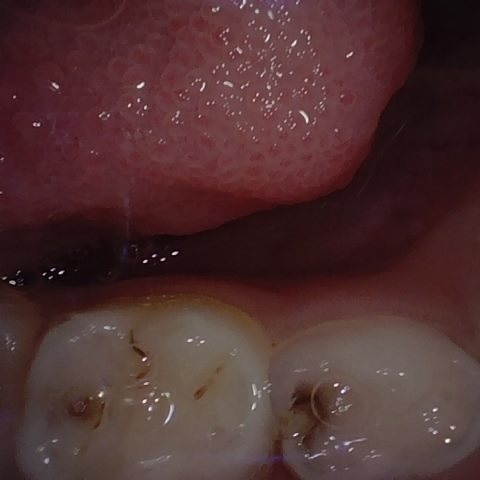

NHD39177

Annotated as "Good"